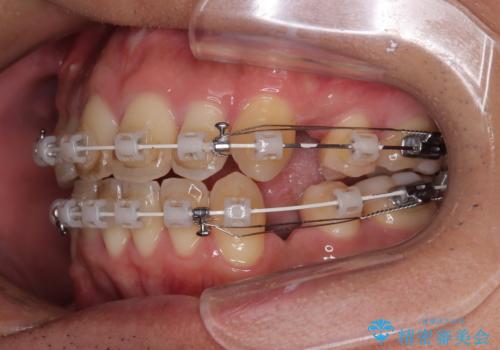

使用した装置は、透明感のあるプラスチックブラケットと白くコーティングされたワイヤー。

金属の装置に比べて目立ちにくく、治療中も自然な見た目を保ちながら矯正を行うことができました。